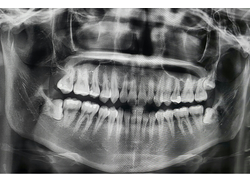

사랑니 발치 후 음식 음주 실밥 제거는 언제쯤 하는지 등 사랑니 발치 후에 대한 정보를 정리해드리도록 하겠습니다.사랑니는 일반적으로 18-25세 사이에 발생하는 어린 시절 치아 중 3번째 대구치를 말합니다. 대개 상아질로 된 이빨과 마찬가지로 식이기구의 역할을 합니다. 하지만 대개 다른 이빨보다 공간이 좁아 자리를 잡지 못하고 다른 이빨과 충돌할 가능성이 높습니다. 이로 인해 충돌로 인한 주변 치아의 이상을 유발할 수 있고, 때로는 발치가 필요합니다. 또한, 사랑니 발치 시 치아 근육통, 치은염, 치아 골수염 등의 문제도 발생할 수 있습니다. 따라서, 꾸준한 치과 검진과 개인적인 구강 관리가 중요합니다.

사랑니 발치는 부분 마취를 진행 후 수술실에서 이루어집니다. 수술 전에는 환자의 건강 상태와 치아의 위치와 상태를 파악하기 위해 치과 전문의가 진단을 수행합니다.

수술 중에는 치과 전문의가 주변 치아와 잇몸을 보호하기 위해 블록 등 잇몸을 보호하기 위한 장치를 사용 사랑니를 뽑게 됩니다.